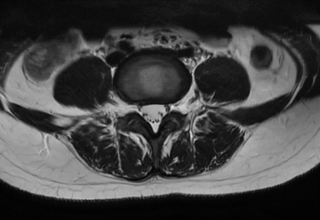

3.MRI(磁共振成像):

优势:无辐射,对软组织(如椎间盘.脊髓.神经根)显示极为清晰,能准确判断椎间盘突出程度.神经根受压情况.脊髓病变等,还可发现隐匿性骨折.软组织肿瘤等。

局限:检查时间较长,体内有金属植入物(如心脏起搏器.金属内固定物)的患者一般不能进行。

适用情况:腰痛伴下肢放射痛.麻木,怀疑腰椎间盘突出.神经根受压.脊髓病变.软组织损伤或肿瘤时。